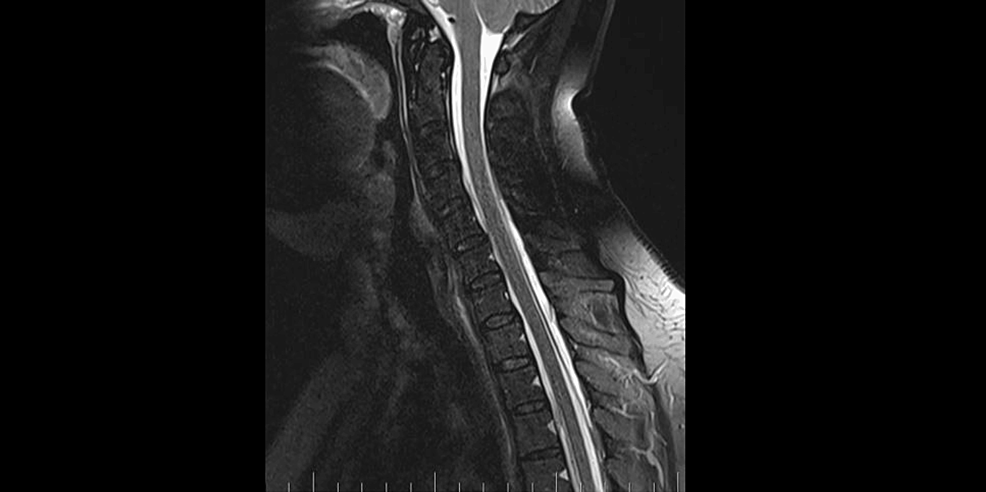

Precisely locating the site of the CSF leakage is fundamental to successful treatment [8]. Hence, on February 2, 2023, we performed a C spine MRI. At the level of C7/T1/T2, a T1 right foraminal CSF leak, as well as the spinal longitudinal extradural fluid collection (SLEC) caudal to the C5 level was detected (Figure 2). This finding confirmed the CSF leak outside the dural sac. It was an SLEC 1b type of CSF leak [4].